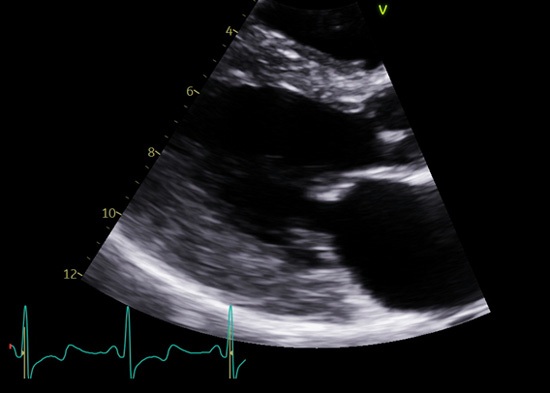

- Échocardiographiques : une hypertrophie VG (≥11-12 mm) (Figure 1) éventuellement associée à une hypertrophie VD, un strain longitudinal abaissé typiquement notamment en inféro-latéral dans les stades précoces (Figure 2). L’hypertrophie est généralement plutôt concentrique, mais parfois, elle prédomine en latéral ou en septal, et parfois, l’atteinte peut être une CMH apicale, et plus exceptionnellement une dilatation ventriculaire (CMD) ou une hypertrabéculation VG excessive (non compaction). Généralement, la FEVG est préservée. On peut observer une dysfonction diastolique, une élévation des pressions, des valvulopathies modérées ;

Figure 1 : hypertrophie ventriculaire gauche concentrique modérée (13,5 mm en latéral) en échocardiographie en cas de maladie de Fabry chez une femme âgée de 40 ans